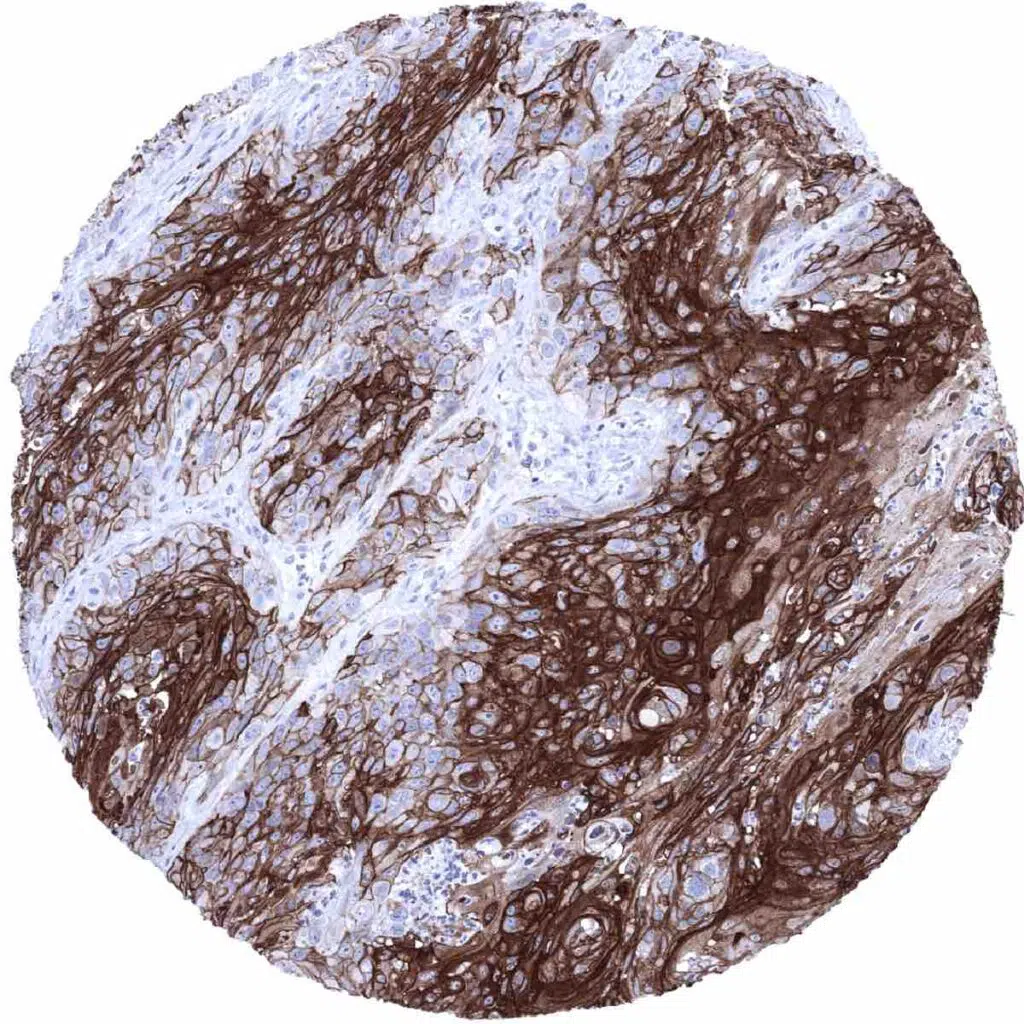

Larynx- Squamous cell carcinoma with intense Dsg1 immunostaining of tumor cells

Larynx- Squamous cell carcinoma with intense Dsg1 immunostaining of tumor cells. Staining is weaker at the periphery of tumor cell nests